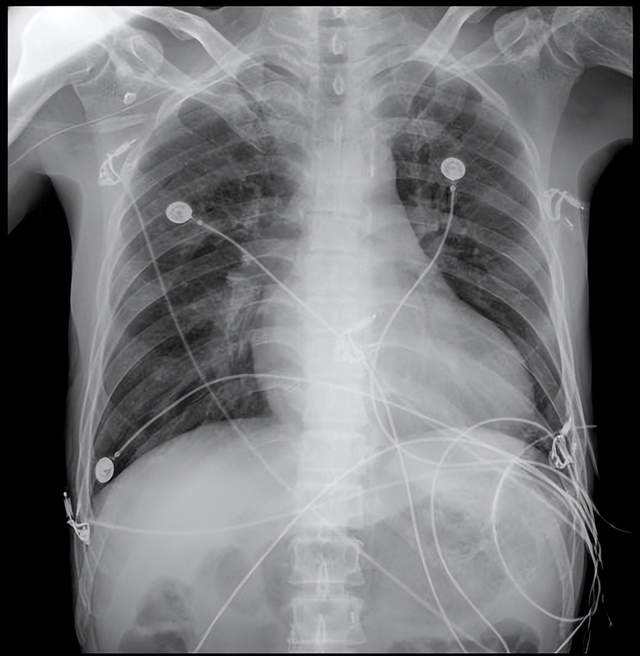

经全面系统检查,张先生被确诊为终末期心力衰竭,同时合并多重严重并发症:难治性心力衰竭D期(心功能IV级,NYHA分级)、冠状动脉粥样硬化性心脏病缺血性心肌病(陈旧性心肌梗死、冠脉支架植入术后)、二尖瓣及三尖瓣重度关闭不全、心房扑动、下肢深静脉栓塞(下腔滤器置入术后),还存在凝血功能异常、肝功能不全、血小板减少等问题,病情复杂危重,传统治疗手段已难以奏效,心脏移植成为唯一救命选择。

3月29日,手术按计划顺利开展。整个手术过程历时约350分钟,所有操作均在9厘米的肋间小切口内完成,成功突破河南省心脏外科微创移植技术瓶颈。

术中,患者在全身麻醉下取仰卧位,右侧胸腔垫高30°,手术团队于右侧第三肋间做小切口进胸,借助胸腔镜辅助切开心包并悬吊,清晰暴露手术视野。随后,团队通过左股动脉、右颈内静脉建立体外循环,同步完成肝素化、下腔静脉置管、左心引流等关键操作,为供心植入创造了稳定的生理环境。与此同时,供心获取与修剪工作同步推进,经精准评估,供心发育正常、冠脉走形良好,为移植成功提供了核心保障。

在胸腔镜放大视野下,手术团队严格遵循“由浅到深、由远及近”的操作原则,精准完成左房、主肺动脉、升主动脉等5个关键血管吻合口的双重锁边缝合。这种精细化操作既确保了吻合口的牢固性,有效避免术后出血风险,又杜绝了血管狭窄等并发症,保障了供血通畅。此次手术升主动脉阻断时间仅99分钟,患者全程生命体征平稳。

术后,患者心率维持在98次/分、血压稳定在111/56mmHg,顺利返回心脏外科重症监护病房,术后恢复进程远超预期。